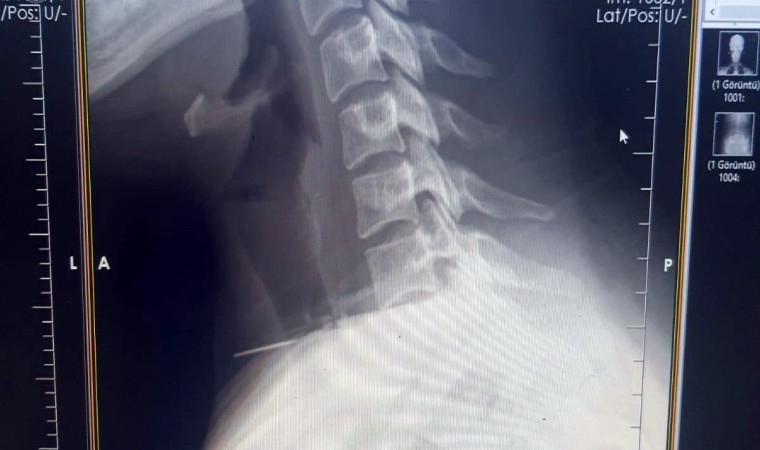

Edinilen bilgiye göre olay, Şanlıurfa’nın Birecik ilçesinde yaşandı. Boğazına dikiş iğnesi saplanan 25 yaşındaki Z.İ., Birecik Devlet Hastanesine başvurdu. Radyolojik incelemeler ve klinik değerlendirmeler sonucunda, 3 santimetrelik iğnenin boğaz bölgesinin derinliklerine doğru ilerlediği tespit edildi. İğne, yaklaşık 1 saat süren ameliyatla çıkarıldı. Ameliyat sonrası süreci sorunsuz atlatan hasta taburcu edildi.